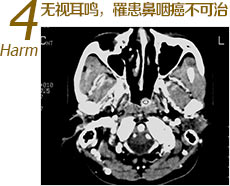

耳鸣也是某些高危疾病的早中期症状之一,中耳肿瘤(如鼓室球体瘤和颈静脉球体瘤)、桥小脑角肿瘤如鼻咽癌、神经紊乱、脑供血缺乏、糖尿病等,若持续耳鸣应当及早就医…>>详细了解